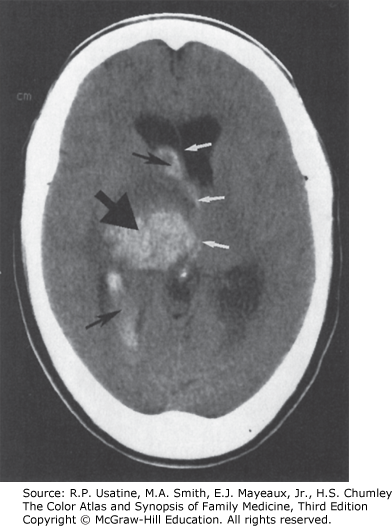

Hemorrhagic stroke. CT image demonstrates bleeding in the right basal ganglia (large black arrow) and into the ventricles (small black arrows). Blood appears white on the CT scan. The white arrows illustrate midline shift. (Reproduced with permission from Chen MYM, Pope TL, Ott DJ. Basic Radiology. New York, NY: McGraw-Hill Education; 2004.)